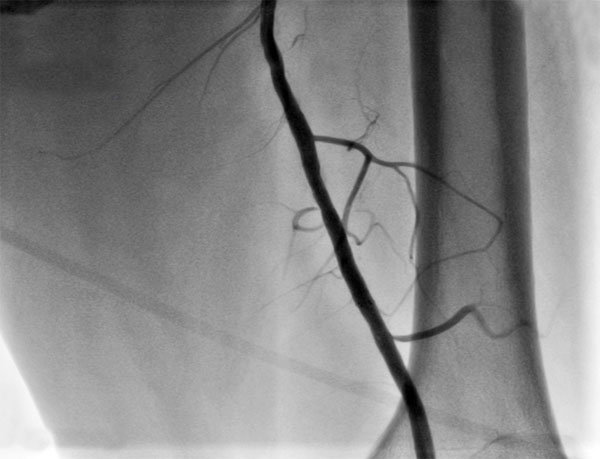

Рис. "Завершение эндоваскулярного этапа - контрольная ангиография: поверхностная бедренная артерия без остаточного стеноза, магистральный кровоток без препятствий, стент раскрыт полностью."